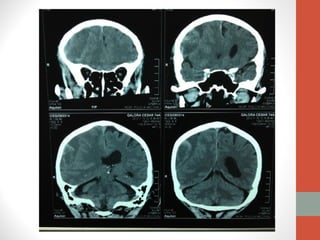

Tomografía

Simple de

Cráneo

Hematoma Subdural Crónico

• Acúmulo de sangre en el espacio subdural.

• Entre la aracnoides y la duramadre.

• Espacio virtual, fácilmente expansible, a costa de colapsar el

cerebro subyacente.

• TAC

• Mayor densidad (más blanca) que el cerebro.

• Sangre, células y otros componentes indican que es relativamente

reciente su formación

• Menor densidad (más negra) que el cerebro.

• Las células y la mayor parte de las proteínas degradadas,

correspondiéndose con un líquido amarillento hiperproteico; indican

varios meses de antelación.